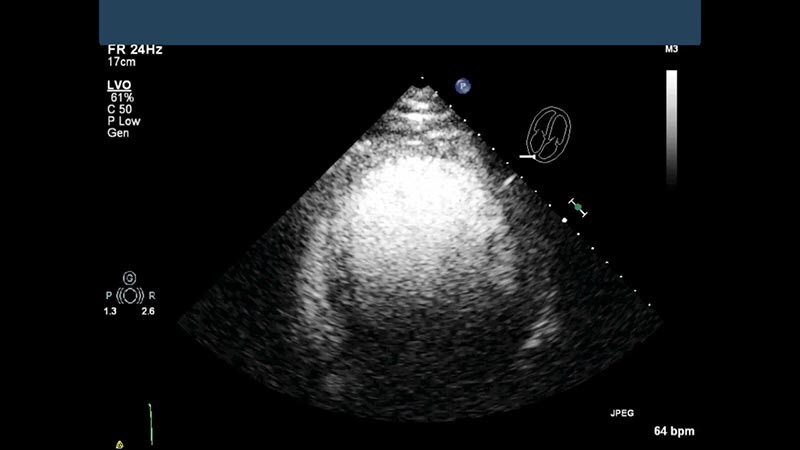

CV Imaging